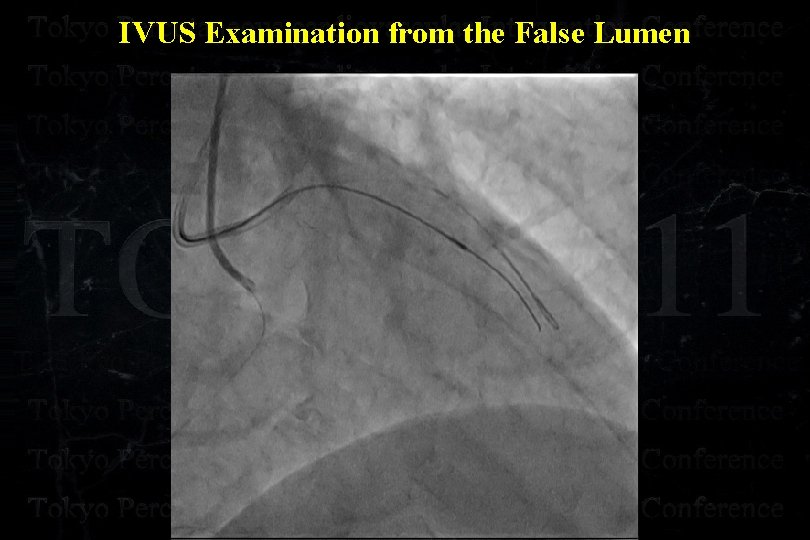

IVUS Examination from the False Lumen